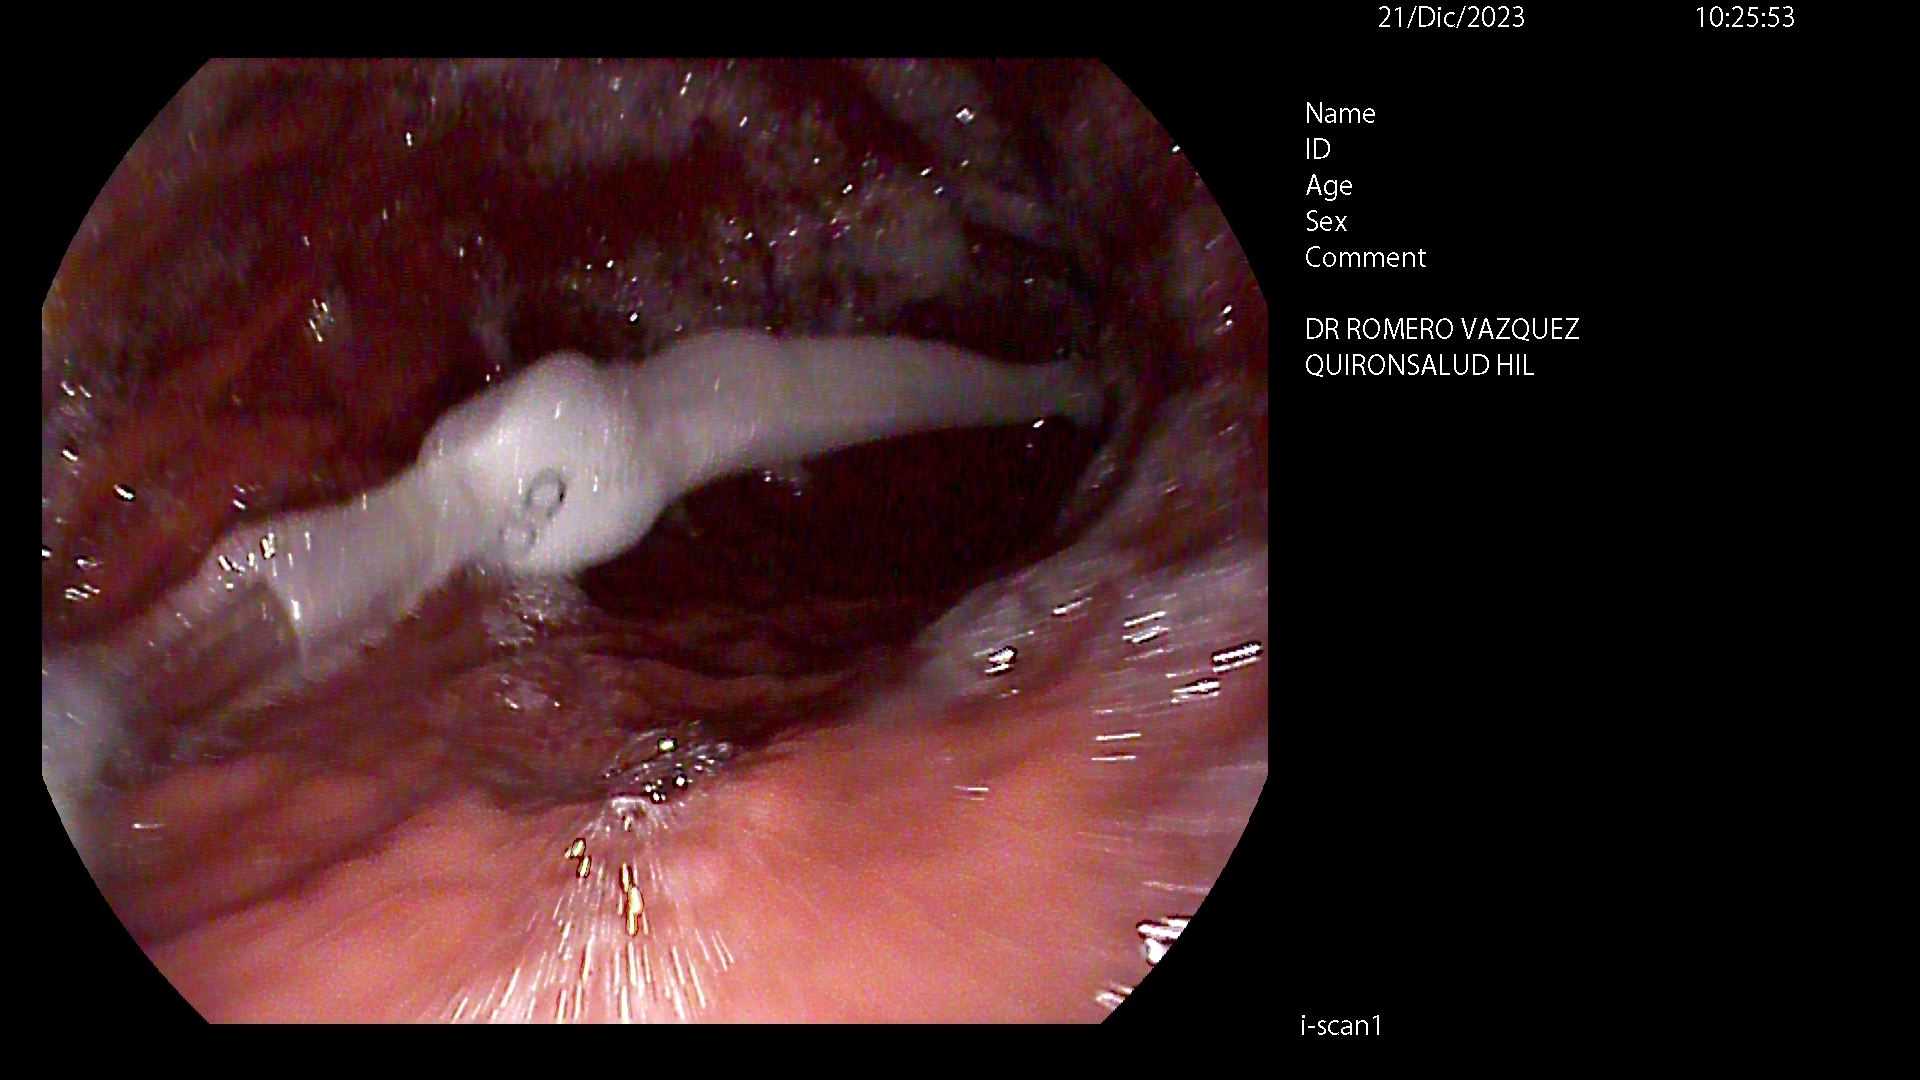

BALÓN INTRAGÁSTRICO

El balón intragástrico es un implante temporal de silicona, que rellenamos con suero, normalmente unos 500-600 cc, con un colorante (azul de metileno) para detectar cualquier posible anomalía futura (pérdida de contenido o rotura), una vez se aloja en el estómago y ocupa una parte importante del mismo. Esto genera dos mecanismos clave para aumentar la saciedad y por ello, perder peso:

Su colocación se realiza en la mayoría de las ocasiones por gastroscopia con sedación profunda administrada y controlada por anestesista, siendo una técnica ambulatoria (no precisa ingreso hospitalario) y su retirada, tras haber cumplido su función a los 6-12 meses, dependiendo de cada caso concreto, por gastroscopia con intubación y anestesista general, para minimizar los posibles inconveniente inherentes a la técnica, igualmente de forma ambulatoria.